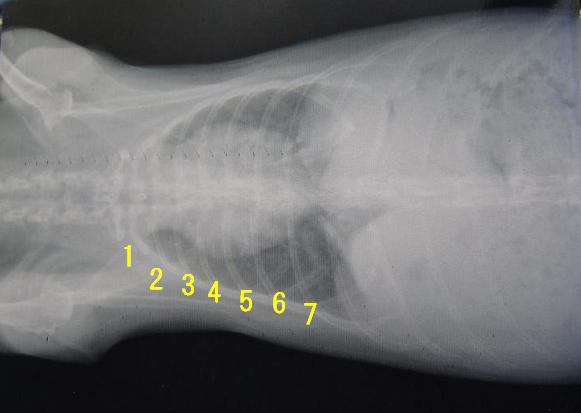

病院のパソコン画面で過去のものと比較した時は、さほど大差なく、

悪化も改善もない感じ?だったのだが…

前回のと見比べると、書き込む数字がえらいことになってるんですけど(;´Д`)

ただ、横からの画像では、そんな大差なく感じる。

何度もレントゲン画像を見ながら、今更な情報ですが、

胸腺の場所は、前より(画像向かって左側)だそうで…。

なので、前回のレントゲン画像を見た時、

その辺りが窪んでる事から明らかに小さくなってる!と先生は明るめに言ったのか。

(喉側にくびれが出来てるのが正常の心臓付近レントゲンです)

まだ、そのくぼみは保たれていたので、

ちなみに、レントゲン画像で見る腎臓は、ツルンとしてなくて

腎臓病である可能性がゼロでは無い、とか…。

(腎臓は向かって上右寄りの部分、データでなく写真でもらうので、

鮮明でなく、上写真では様子はわからないと思います。)

ムッちゃんの腎臓は少しモヤがかった輪郭があるように見えた。

それが先生の言う“ツルン”なのか、ちょっとよくわからないのだが、

正常な腎臓は、何せ“ツルン”となってるらしい( ̄∀ ̄;)

で、“ツルン”となってなくても、働きに問題のない腎臓も多いので、

心臓病か否かの判断は難しく、レントゲン画像では、肺や気管の様子も気になると。

肺の周りに小さな丸い空洞が見えてて、気管支炎とかって可能性もある。やったかな…

パソコン画面で、空洞を見せてもらって「ぅゎホンマや」て思った所しか覚えてへん(;´Д`)